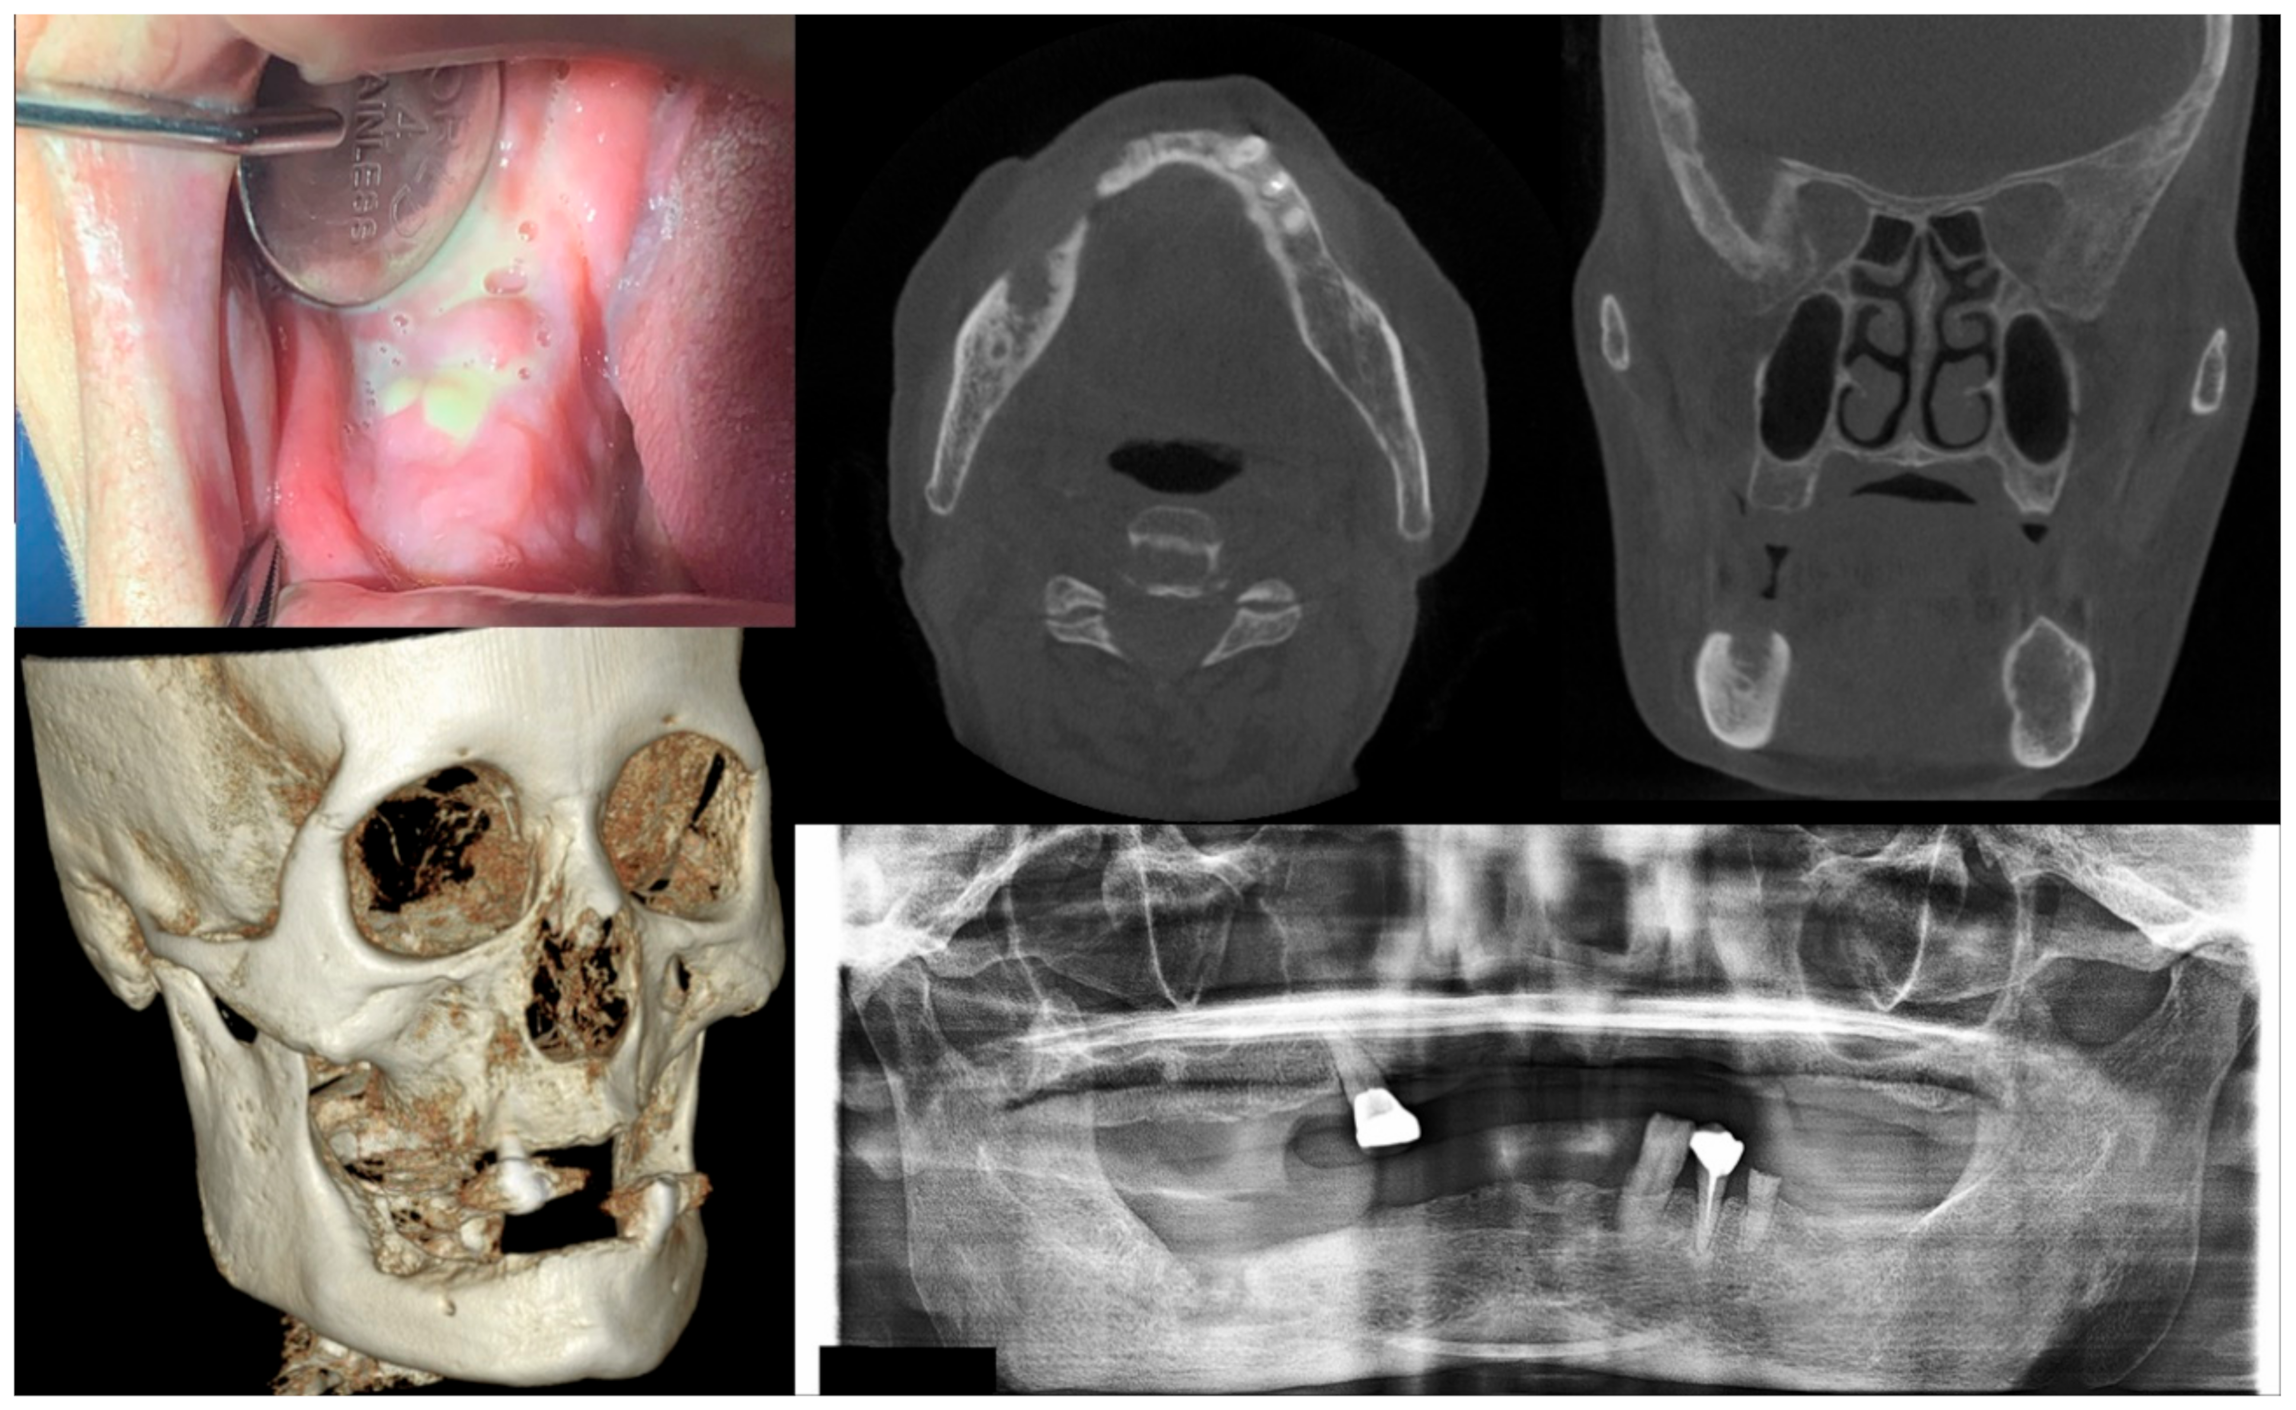

Figure 3.

Case 3 with MRONJ Stage 2: Clinical photo, panoramic view, and computed tomography imaging including three-dimensional reconstruction showing exposed alveolar bone with pus discharge on the right mandibular posterior area. A 68-year-old female patient with a history of intravenous administration of ibandronate for eight years and intravenous administration of denosumab for the last year complained of facial swelling, severe pain, and pus discharge. She had undergone extraction of the right lower second molar at the private dental clinic to relieve the facial swelling and pain. Symptoms were relieved slightly after extraction but worsened again after two weeks. As a result of the examination, exposed bone and infection signs were observed.